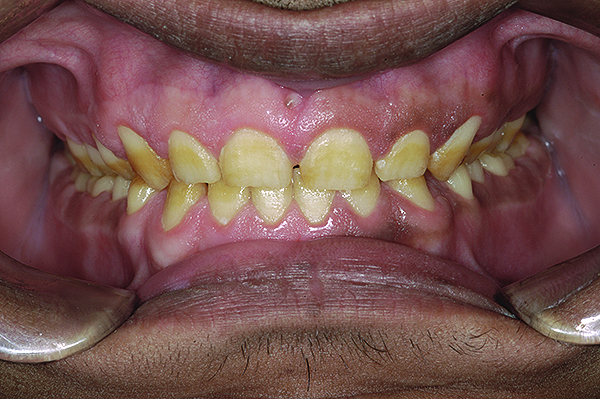

Figure 1. Preoperative frontal smile of patient suffering from AI, showing small, discolored, worn teeth.

Figure 1

The authors report on a 21-year-old patient who presented with severe discoloration and mild sensitivity of teeth (Figure 1). The teeth visible in his smile were very short, unsightly, and unbecoming for his age.